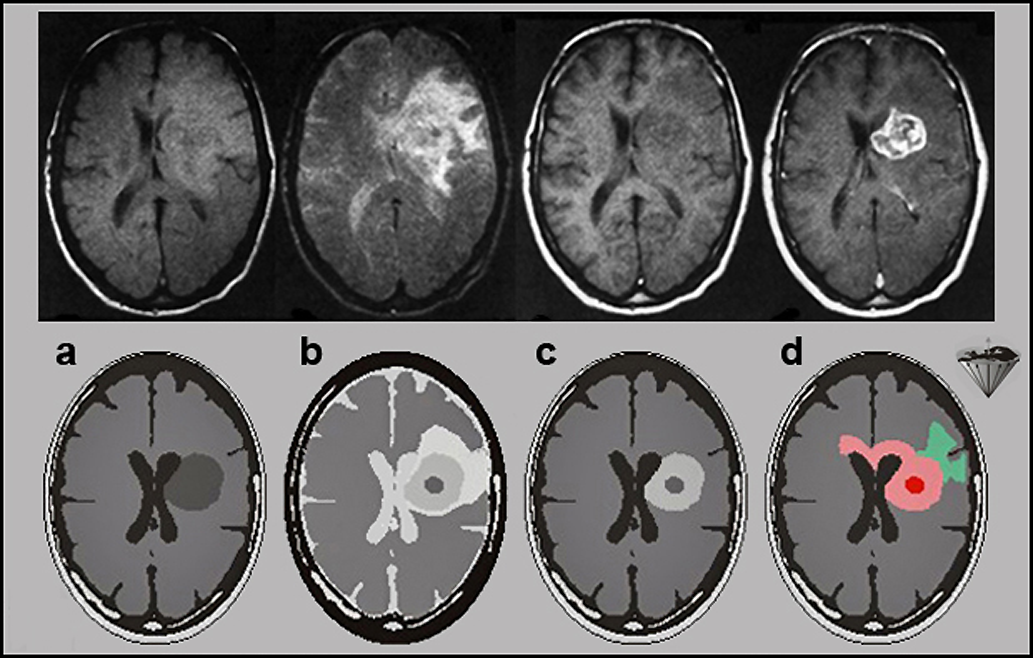

Figuras 13-11:

Top row: Malignant brain tumor.

(a) proton-density-weighted image; (b) T2-weighted image; (c) T1-weighted precontrast image; (d) T1-weighted postcontrast image.

Although it is obvious that a large mass displaces the lateral ventricles, an exact delineation of the tumor is impossible on the first three images. Edema is well seen on the T2-weighted ima­ge, but the dark tumor areas are poorly delineated. Only after the contrast agent administration does the tumor become bright and its active parts are well visible.

Bottom row: Graphic explanation of corresponding histology. The contrast agent only en­han­ces ab­sence or breakdown of the blood-brain-barrier and high-vascularity lesions.

(a) and (b) T1- and T2-weighted precontrast images of a highly malignant tumor similar to the one seen in the top row; (c) the T1-weighted postcontrast image — corresponding to (d) in the top row; and (d) the actual microscopic tumor extension through the corpus callosum, which is not divulged by the MR images. The enhanced image shows only the tumor region, with the effect on the blood-brain barrier.